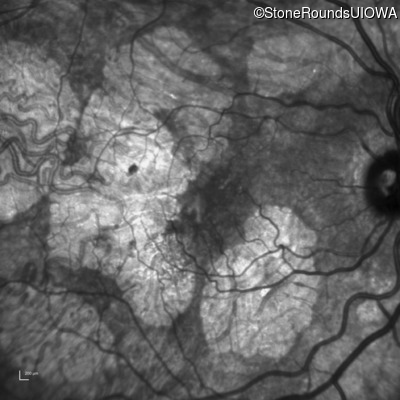

AR Stargardt Disease (IIA)

Age at visit: 55 years

Diagnosis & molecular findings

Disease Gene Allele 1 variant(s) Allele 2 variant(s) Inheritance mode

AR Stargardt Disease ABCA4 Gly1507Arg GGG>AGG IVS42+1 G>A AR